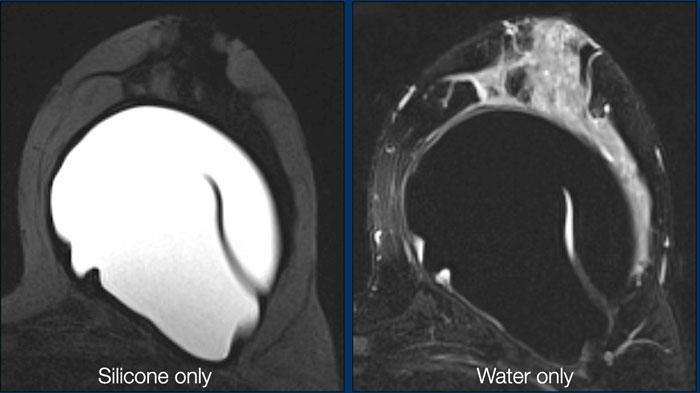

Hình ảnh chỉ hiển thị Silicone

Đây là chuỗi xung STIR, trong đó mỡ bị ức chế, kết hợp với ức chế tín hiệu nước. Kết quả là chỉ còn tín hiệu của vật liệu silicone. Chuỗi xung này lý tưởng để khảo sát tình trạng vỡ vỏ túi và phát hiện silicone nằm ngoài vỏ túi hoặc ngoài bao xơ.

Hình ảnh chỉ hiển thị nước

Sự kết hợp giữa bão hòa mỡ và ức chế silicone cung cấp thông tin về các ổ dịch tụ bên trong hoặc xung quanh túi độn.